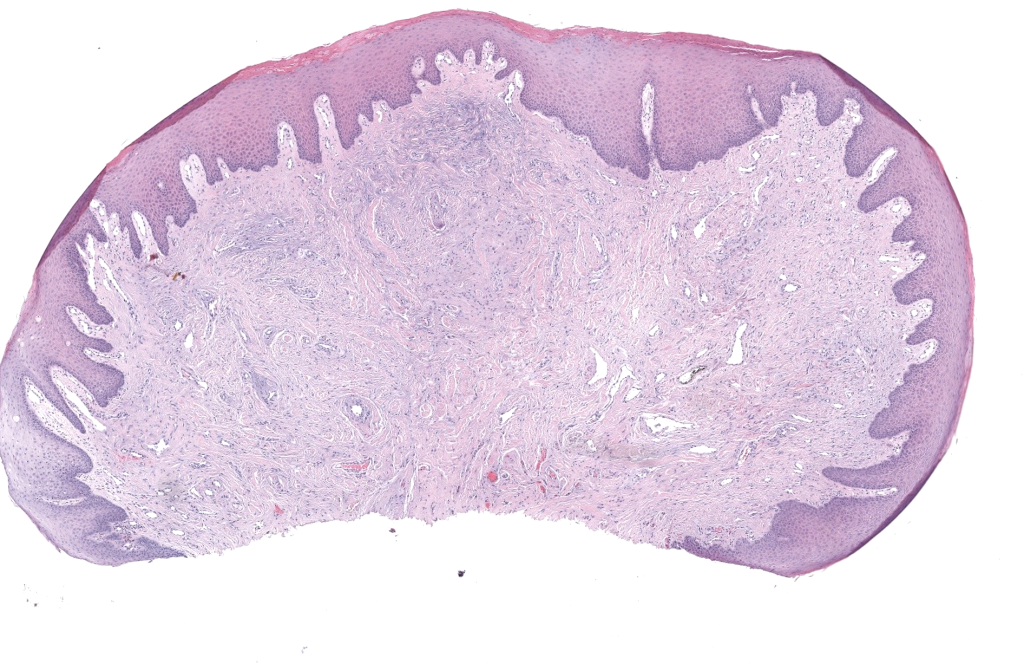

- Histología: hiperqueratosis, acantosis, colágeno grueso vertical, fibroblastos blandos, capilares finos, sin atipia significativa.Kint 1985,Wang 2024